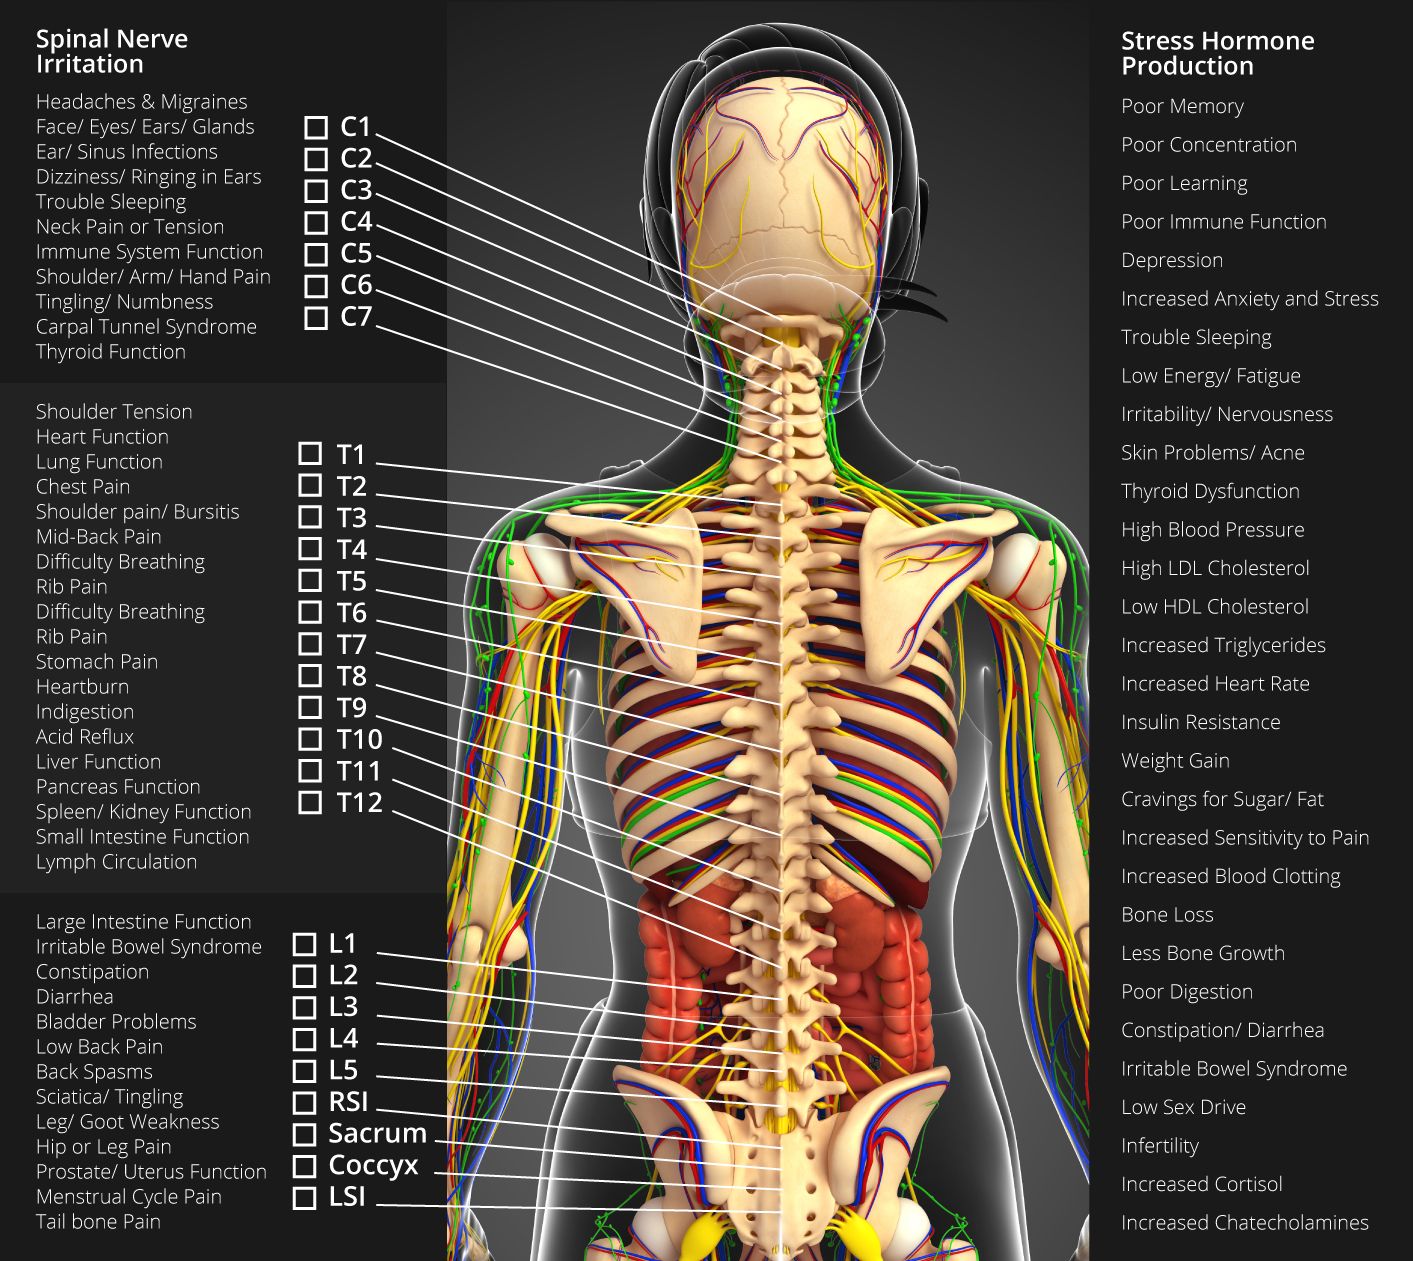

Pin by Michelle Evans on med school | Spinal cord, Spinal nerves …

Out with the Old-In with the New: Chiropractic Care-Why Your Health …

About » Fircrest Family Chiropractic Center

Pin on A&P – CNS

Pin by Allison Atwill on OT Grad in 2021 | Spinal cord, Spinal cord …

anatomy+of+the+sciatic+nerve | Nerves Of Spine | Healing remedies …

spine+diagram | SPINAL NERVES & EFFECTS CHART | Nursing | Anatomia y …